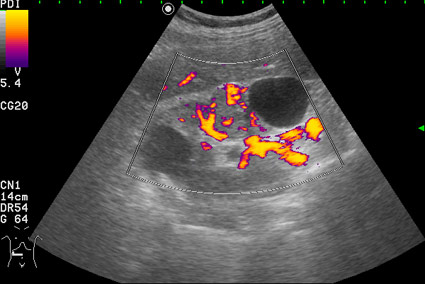

Изменения правой почки у мужчины 56 лет - кисты и RCC

Профилактический осмотр.

Как трактовать выявленные изменения? Какова тактика врача УЗД в данной ситуации?

Вас не смущает наличие внутреннего кровотока в одной из "кист"?

При гистологии эта структура была почечно-клеточным раком (RCC).

Согласен, но есть совокупность признаков, позволяющих с очень высокой степенью достоверности считать, что это тканевое образование, а в отношении конкретного случая - что это почечноклеточный рак (RCC).Uzgraph писал(а):УЗИ не метод гистологической верификации - по УЗИ рак не ставят.

Но Вы правы в том, что могут быть трудности в дифференциальном диагнозе между AML и RCC малых размеров (в 20-30 % случаев могут быть эхогенными). Однако при УЗИ для RCC характерен гипоэхогенный ободок, внутриопухолевые включения, низкорезистивный внутриопухолевый кровоток.